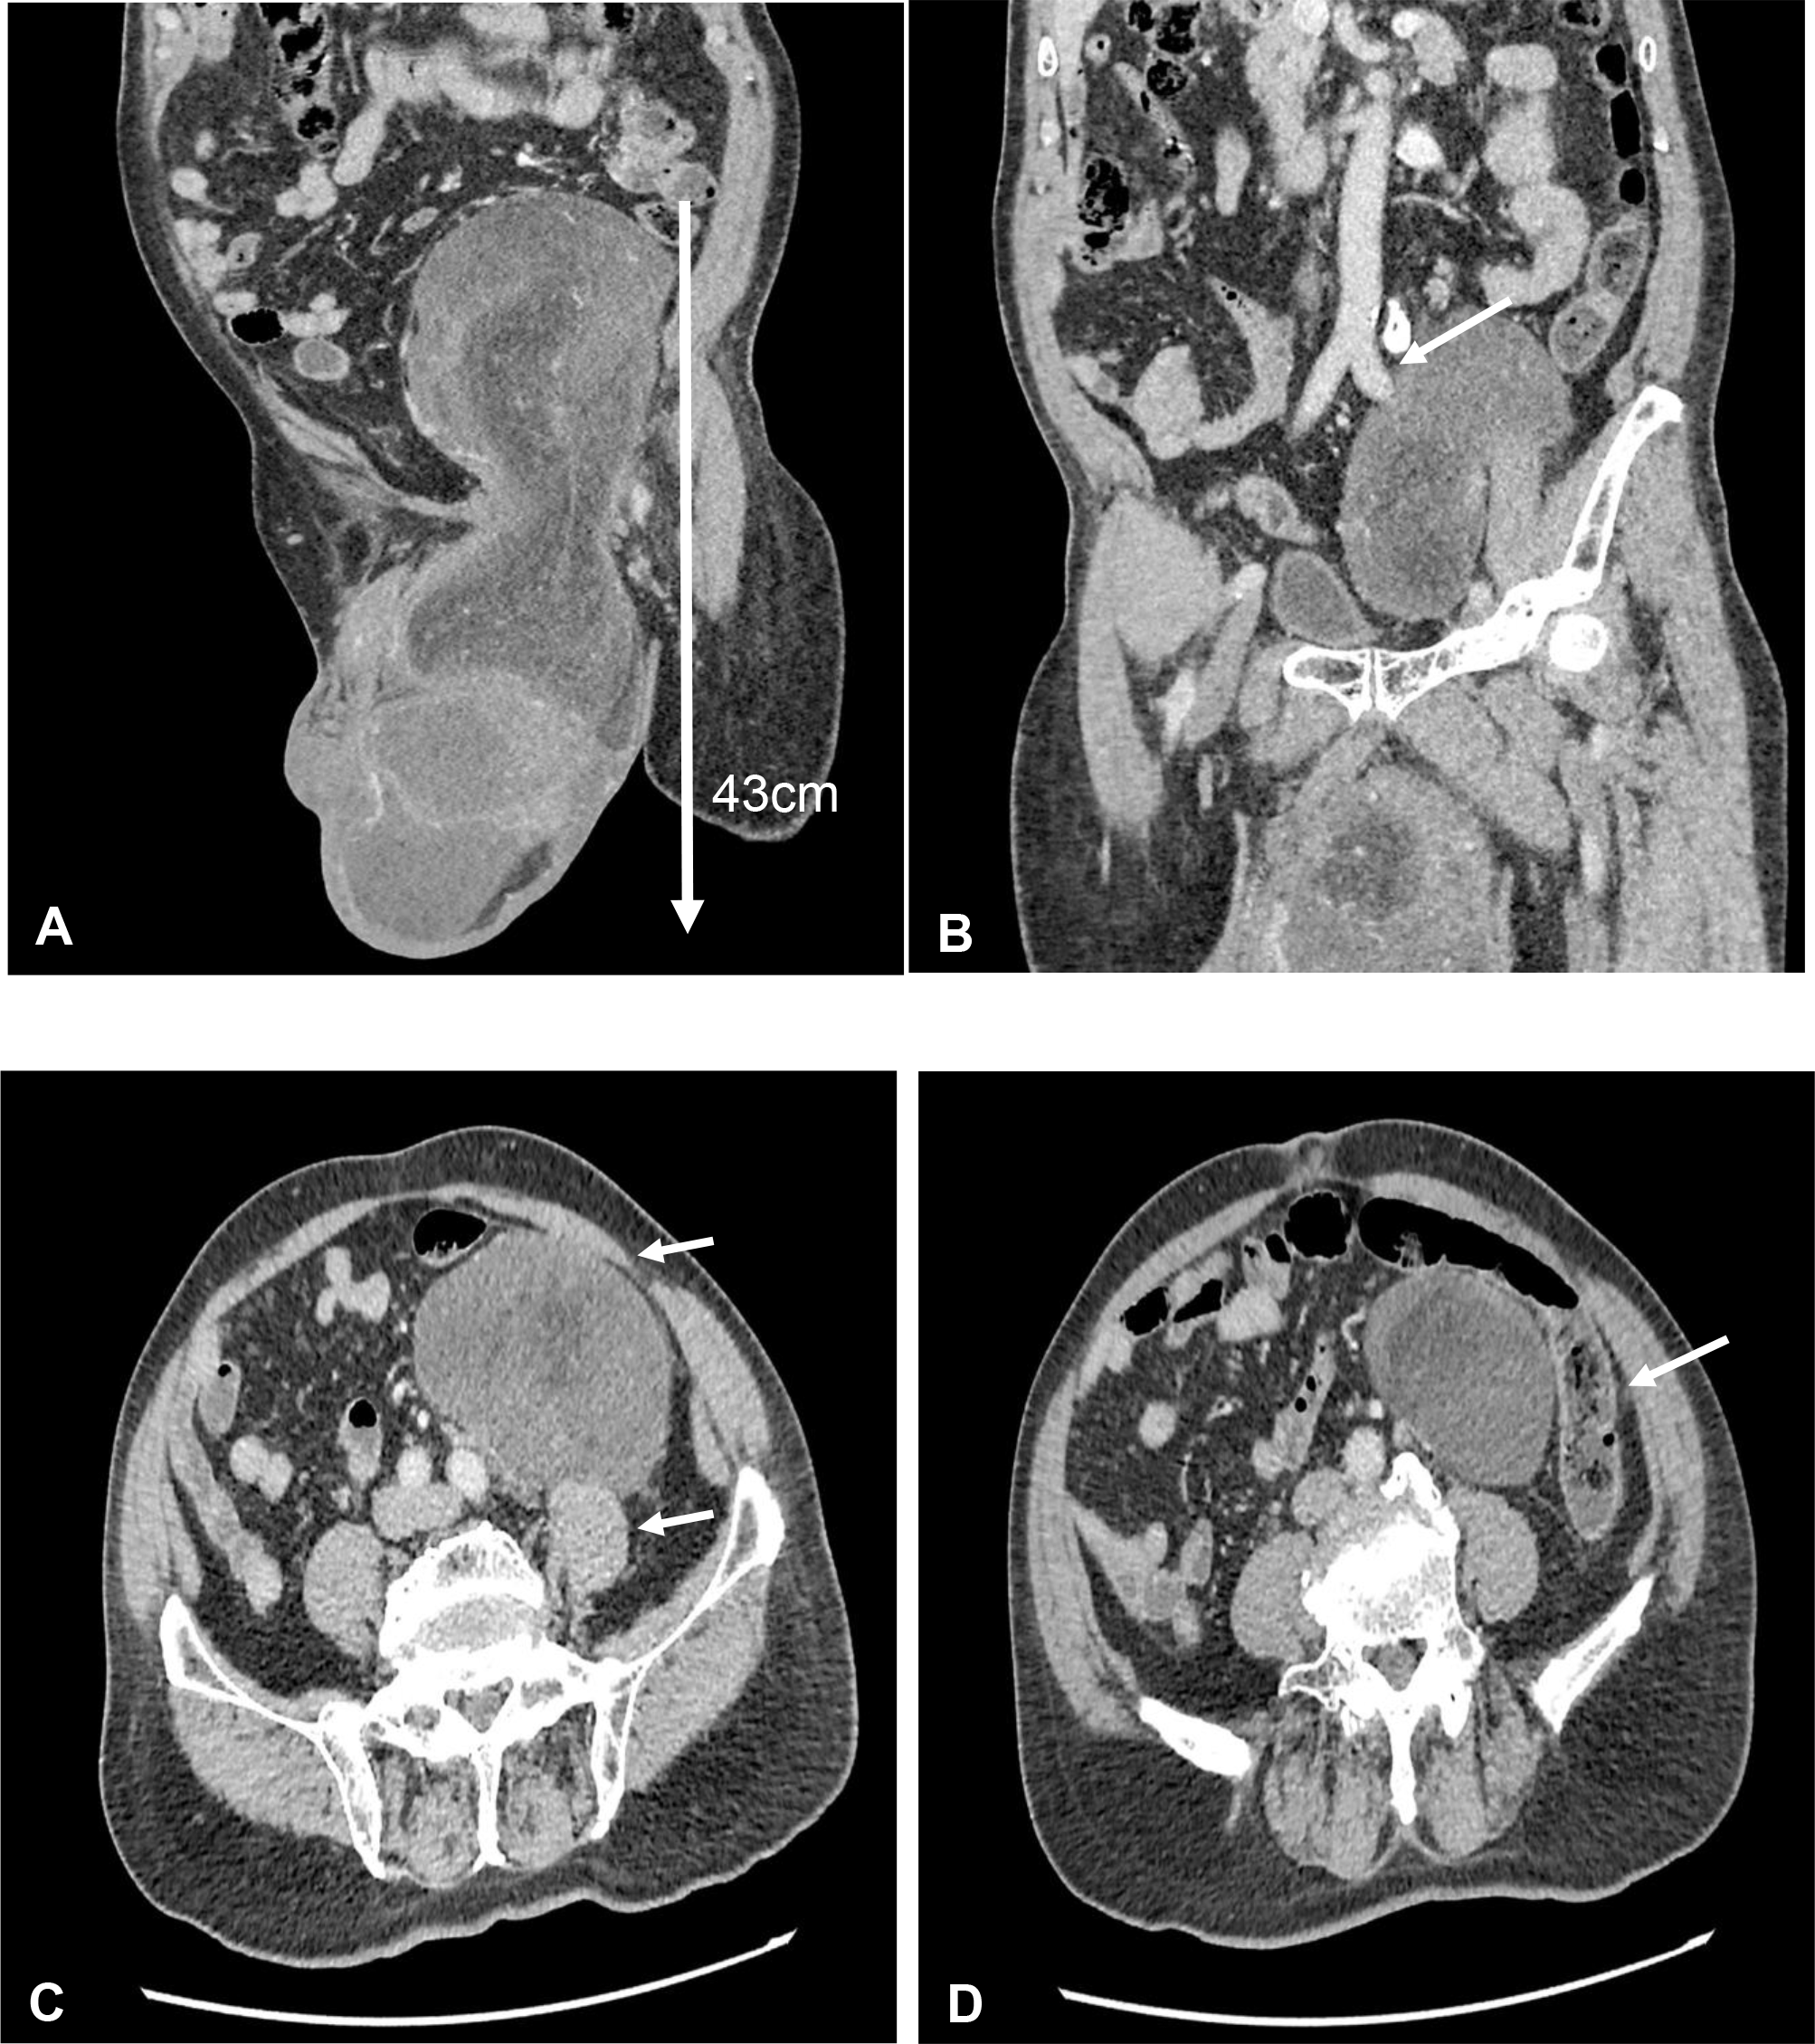

Figure 2

(A) Coronal view of contrast-enhanced computed tomography (CECT) scan showed huge left testicular tumor extending from scrotum until intraabdominal up to umbilical level with a length of 43 cm. (B) Coronal view of CECT scan showed the testicular tumor encasing the left external iliac artery. (C) Axial view of CECT scan showed close proximity to left psoas muscle and anterior abdominal wall. (D) Axial view of CECT scan showed close proximity to the descending colon.

On clinical examination, there was a huge inguinal scrotum tumor that was palpable up to the umbilical level, measuring approximately 50 × 20 × 10 cm (Figure 1). The tumor was hard, non-tender, non-pulsatile, and not expanding with cough impulse. Contrast-enhanced computed tomography (CECT) scan of the thorax, abdomen, and pelvis showed a huge well-encapsulated heterogeneous mass seen within the left scrotum extending to mid-abdomen measuring approximately 42.7 cm in length. It was in close proximity with anterior abdominal wall anteriorly as well as the left psoas and left external iliac artery posteriorly. There was no lymph node involvement and no distant metastasis reported (Figure 2). Serum beta-human chorionic gonadotropin (β-HCG) level was <2.3 mIU/ml and α-fetoprotein (AFP) was over 2.74 ng/ml, while serum lactate dehydrogenase (LDH) was 224 IU/L. The provisional diagnosis was left paratesticular tumor.